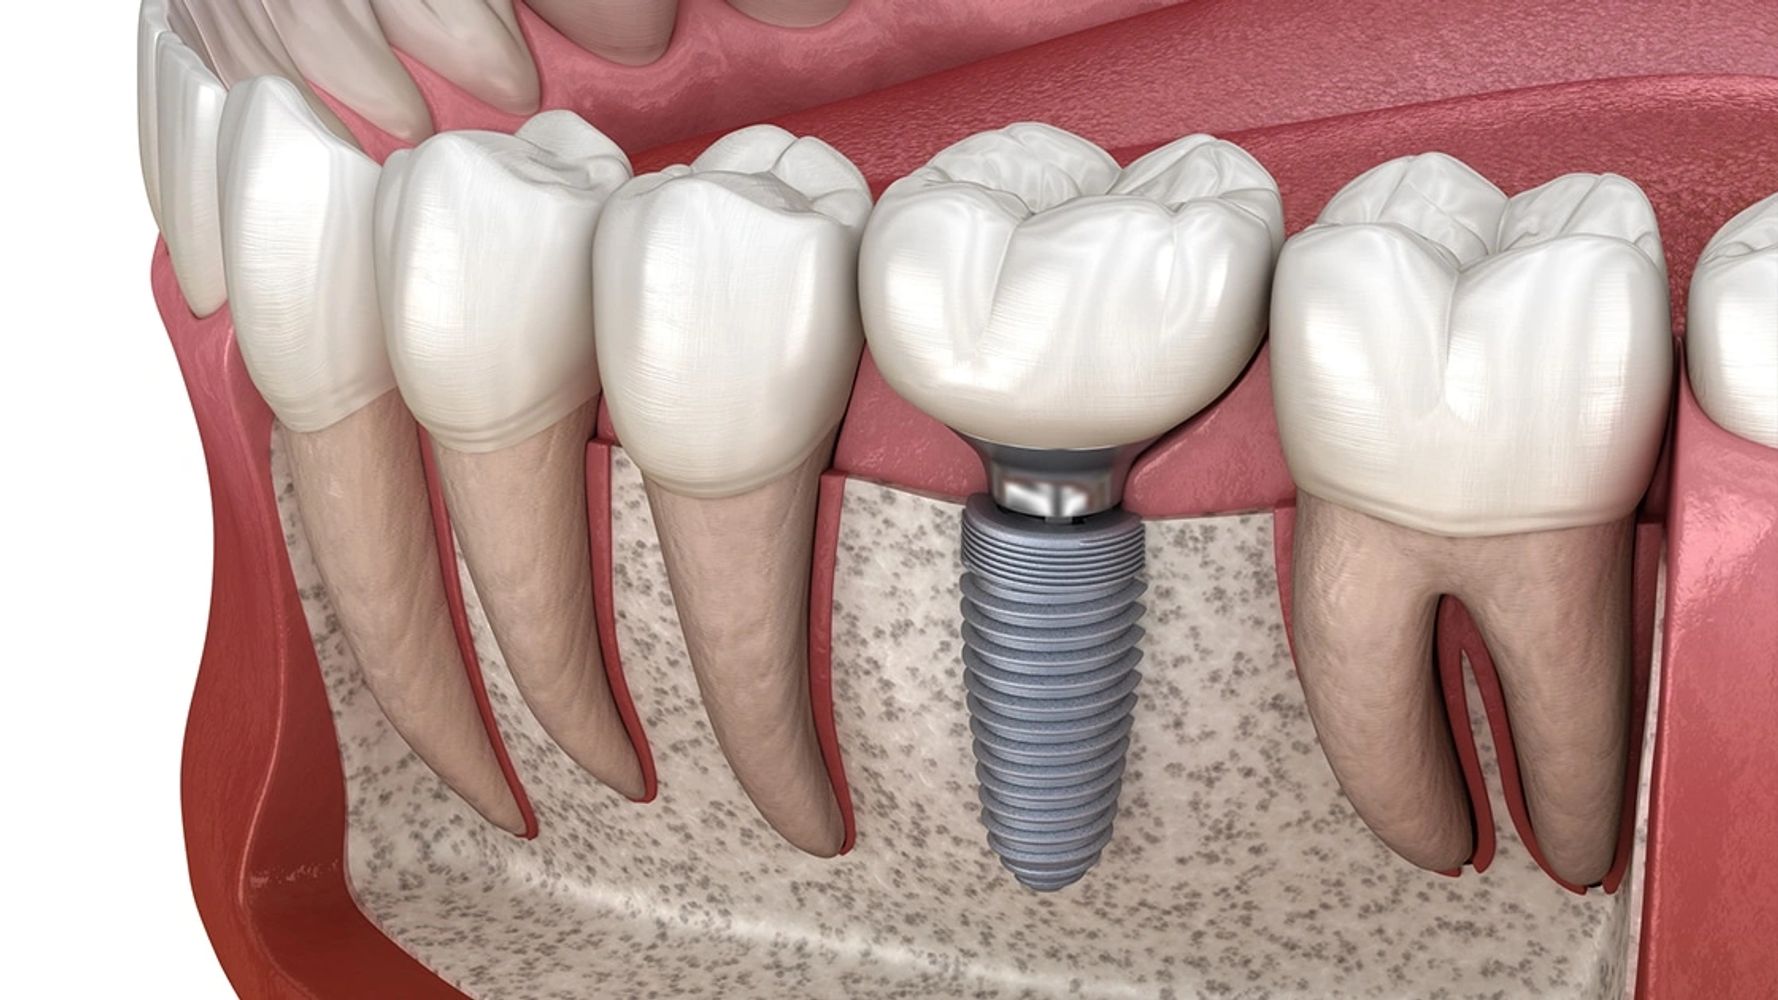

Dental implants are a predictable way to replace missing teeth. Dental implants support oral health by preserving jawbone, stabilizing neighboring teeth, and restoring natural chewing function for a lasting, confident smile.

Dental implants may be indicated to provide stability and retention to dentures.

Immediate implant treatment is the placement of a dental implant immediately after extraction. This will shorten treatment time and reduce the number of surgical procedures.

Dental bridge is another way to replace missing teeth.